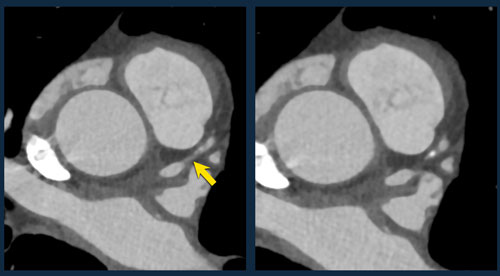

Coronary Artery Disease-Reporting and Data System 2.0

CAD-RADS 2.0